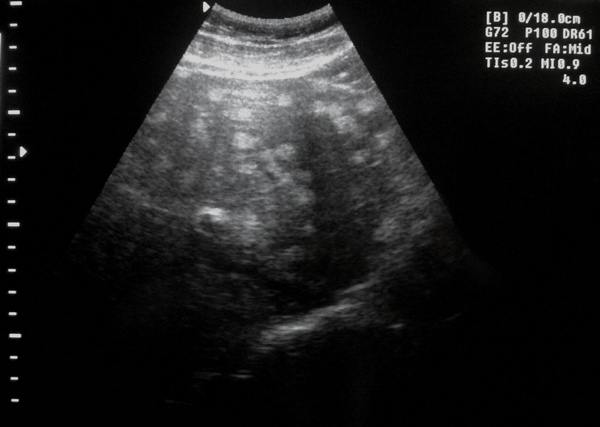

Мужчина,43года. Жалоб не предъявляет

В заключении предыдущего осмотра- Липоматоз печени. Я ранее с таким понятием не встречалась :?:

Вспоминая "немецкий" семинар - Гемангиоматоз?

По имеющимся у меня сведениям, пациенту выполнена КТ (предположены мтс), затем кор-биопсия (данные не в пользу мтс, скорее в пользу гемангиом).

Подождем что напишут коллеги из ВОКОД.